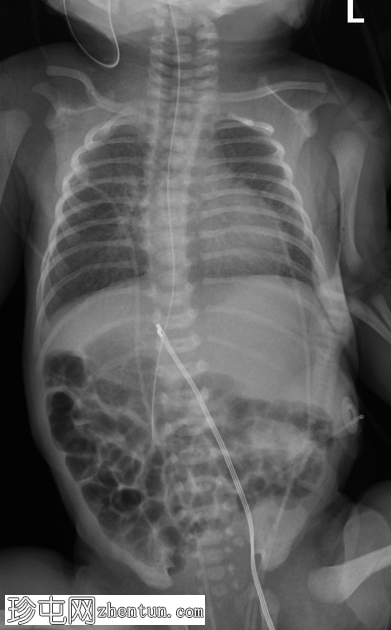

本例为腹腔内脏反位合并肠旋转不良。

初始胸片显示心脏轮廓解剖结构正常。相比之下,腹部X线片显示提示内脏反位的征象,表现为食管造影管的走行异常以及肝脏轮廓明显偏左。透视检查进一步证实了这些观察结果,并进一步提示肠旋转不良。

随后,患者被送入手术室行肠旋转不良手术。术中发现与影像学检查结果相符,证实存在腹部内脏反位和肠旋转不良。具体而言,肝脏、胆囊、门静脉和十二指肠后胆总管位于左侧,而脾脏、胃和胰尾位于右侧。此外,还观察到十二指肠和盲肠之间存在Ladd带,符合肠旋转不良的诊断。